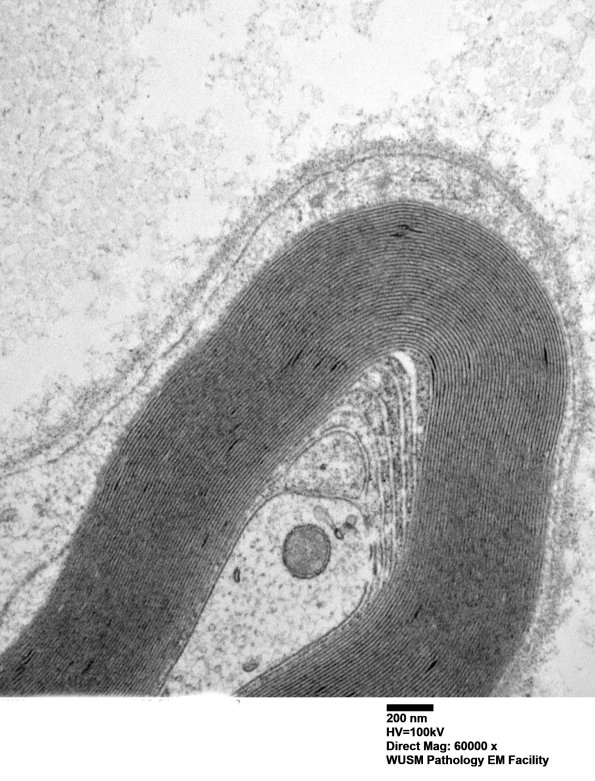

Washington University Experience | PERIPHERAL NEUROPATHY | 13 POEMS SYNDROME | 1C1 (Case 1) Sural_008 - Copy

1C Series of images. In this case POEMs type changes are limited and possibly mimicked by Schmidt-Lanterman clefts. By itself would these changes establish a POEMS case? ---- 1C1 Is it possible to confidently assign this UCM to the coexistent POEMS known for this case. (electron micrograph)